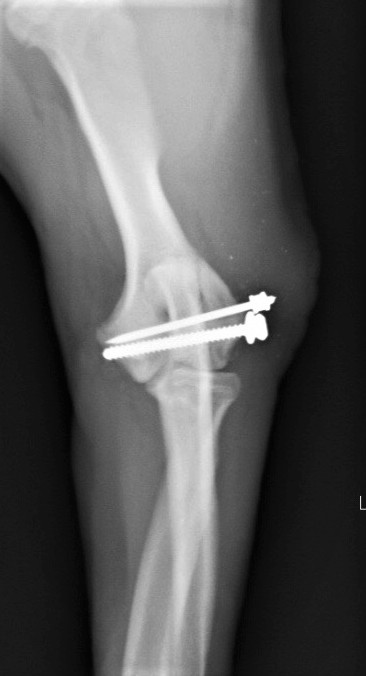

成長版骨折ということもあり早期の手術が必要と判断し、そのまま入院・手術となりました。 肘部の外側からアプローチを行い、肘関節を露出します。 骨折部位を確認し、ピンニングによって仮固定を行います。 Cアームを用いて骨折部位のアライメントが整っているのを確認した後にスクリューを入れていきます。

スクリューとピンの固定後、X線検査にてアライメントが整っているか確認して終了です。